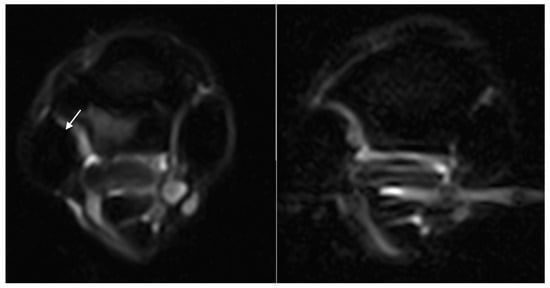

| McIII hyperintense STIR signal | 16/18 (89%) | 16/16 (100%) | - | - | - |

| McIII hyperintense STIR signal | Grade 0: 2 limbs Grade 1: 5 limbs Grade 2: 3 limbs Grade 3: 8 limbs | Grade 0: 18 limbs Grade 1: 0 limbs Grade 2: 0 limbs Grade 3: 0 limbs |